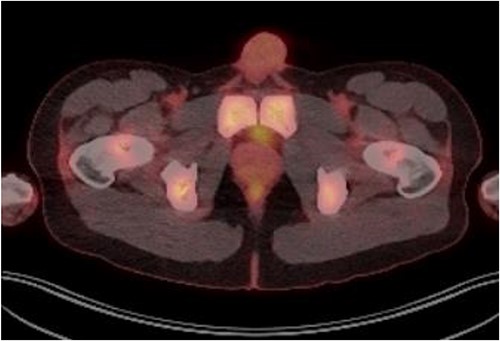

Patient was catheterised and subsequently underwent bilateral ureteric stenting. Cystoscopic views of the prostate was also abnormal and concerning for malignancy, so transperinal prostate biopsy was performed. Histology of this confirmed diffuse large B cell lymphoma. Renal function improved post ureteric stenting and patient was referred to haematology for management of DLBCL. Progress FDG PET scan (Fig. 4) 3 months post R-CHOP chemotherapy showed complete metabolic response with no avid residual lymphoma.

PET FDG scan post R-CHOP chemotherapy showing prostate with complete resolution from the disease.